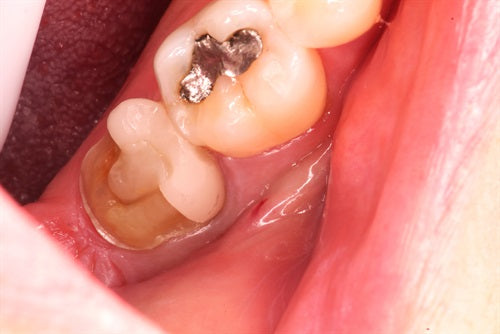

Recurrent caries under crown - "Thinking outside of the box" by Dr. Ahmad Fayad

Introduction: This case was completed by Dr. Ahmad Fayad of Lessard Dental located in Alberta, Canada. Food impaction area that caused massive carious lesion at the distal of the lower... Read More